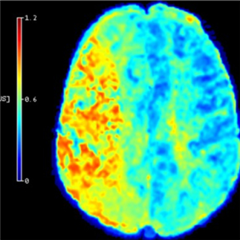

Améliorer la prise en charge des AVC

Une équipe de recherche a développé une méthode qui permet, à partir des images d'IRM de patients ayant subi un AVC, d’améliorer l’évaluation des zones du cerveau pouvant récupérer après un traitement de reperfusion. Ces résultats ouvrent la voie à une meilleure prise en charge des patients, en particulier de ceux jugés parfois inéligibles à ce genre de traitement. Ils sont publiés dans la revue Stroke.